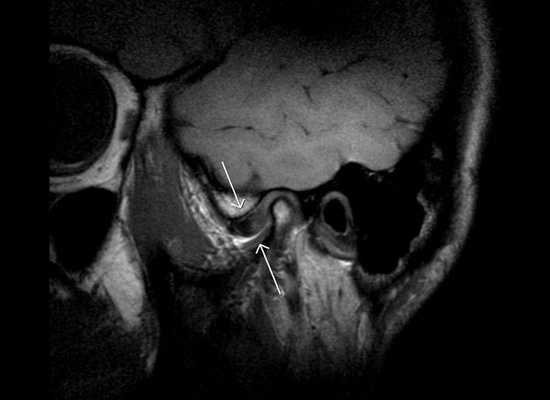

КТ черепа (3D-рендеринг). Прогнатический прикус, зубы верхней челюсти (красная стрелка) выстоят кпереди, отсутствует контакт резцовых краев при смыкании.

КТ черепа. Прогнатический прикус, зубы верхней челюсти (красная стрелка) выстоят кпереди (этот же пациент).